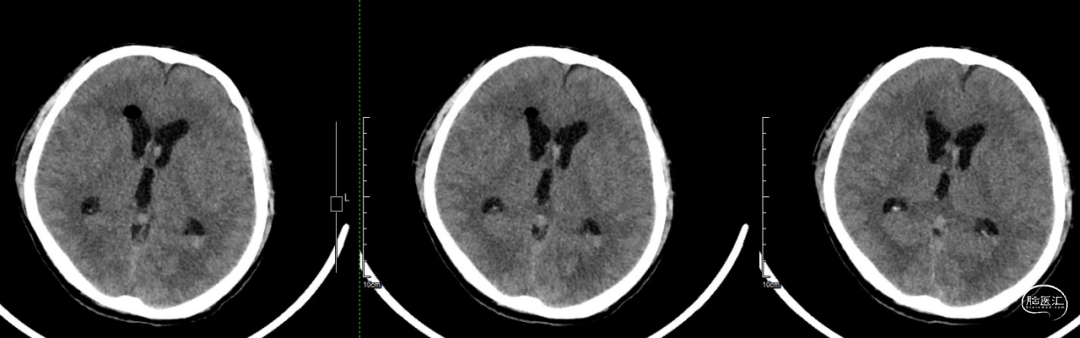

术后当天CT:肿瘤全切,术区无出血,幕上脑室积血,考虑术中出血倒灌所致。

术后一周CT:脑室积血基本吸收。